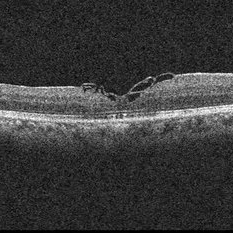

Macular Hole POD 1 OCT

POD 1 - hole closed as seen on OCT

Condition/keywords: full thickness macular hole, optical coherence tomography (OCT)